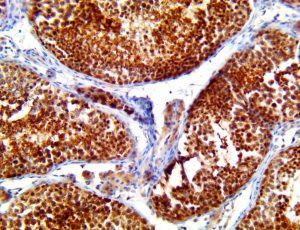

It is the ICU physician who is most likely to witness one of the deadliest manifestations of the abnormal immunological response, the cytokine storm syndrome (CSS). This response is also referred to by some as the cytokine release syndrome (CRS). CSS is characterized by continuous activation and expansion of macrophage and lymphocyte populations, which secrete large amounts of cytokines, causing the cytokine storm. This massive cytokine release is akin to hemophagocytic lymphohistiocytosis (HLH) disease, a syndrome characterized by initial unchecked and persistent activation of cytotoxic T lymphocytes and NK cells.

Clinical and laboratory manifestations of HLH include fever, enlarged liver and/or spleen, neurologic dysfunction, coagulopathy, liver dysfunction, cytopenias (i.e., low levels of erythrocytes, leukocytes, and/or platelets), hypertriglyceridemia, hyperferritinemia, hemophagocytosis, and eventually diminished NK cell activity as the immune system becomes progressively paralyzed. HLH can be familial (primary HLH) or secondary to another disease process (sHLH), such as rheumatic disease, in which it is referred to as macrophage activation syndrome (MAS, characterized by elevated ferritin).